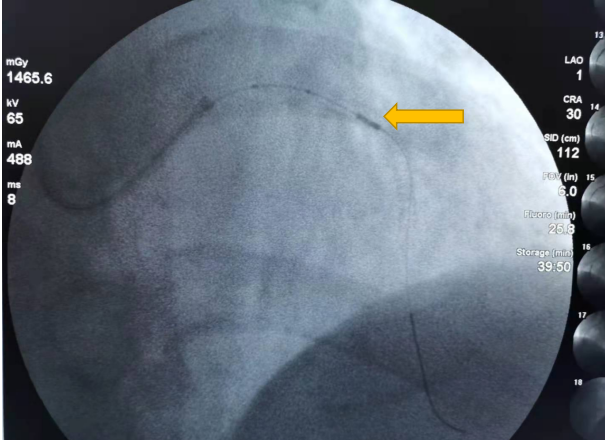

经过近一小时的紧张手术后,成功对病变处予以精确处理。术后复查IVUS,提示实际测得有效官腔直径2.7mm,钙化环已打开、有效血流面积4.0mm²,取得了非常好的治疗效果。术后患者安全返回病房,生命体征平稳,症状明显缓解,患者及家属对手术治疗效果非常满意。

术后1

术后2